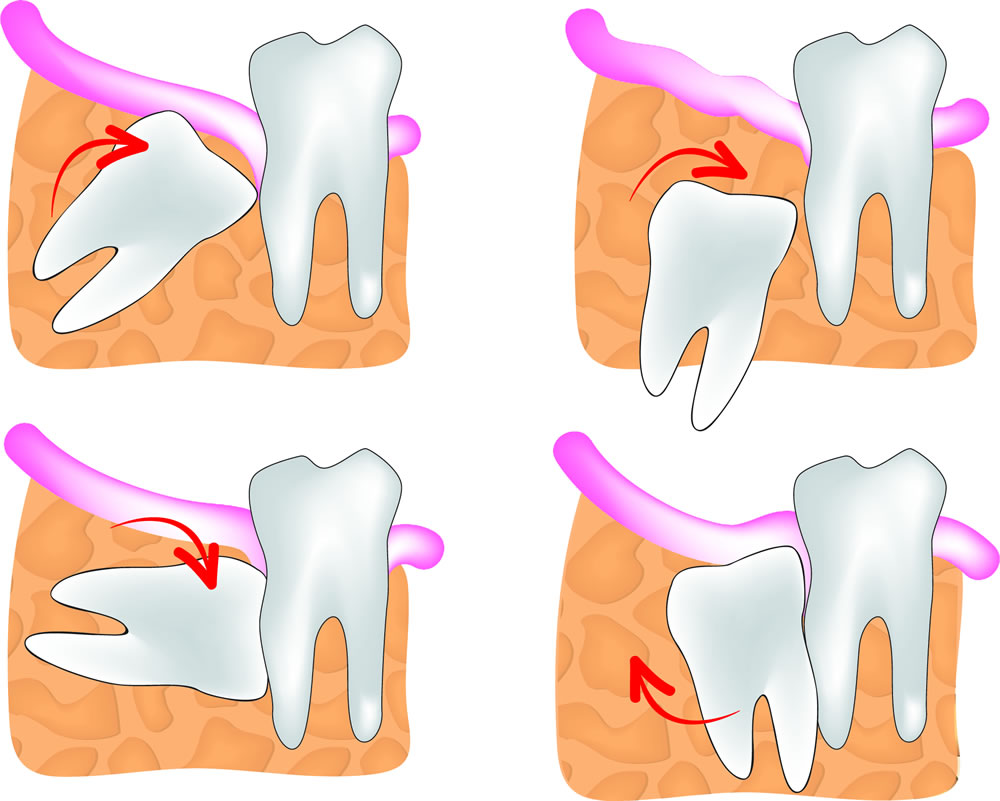

Có rất nhiều phân loại răng khôn khác nhau như phân loại của Winter, phân loại của Pell & Gregory. Tại Việt Nam trong các bảng giá nha khoa hẳn nhiên các bạn sẽ thấy có những hạng mục như nhổ răng khôn mọc kẹt, mọc lệch 45 độ, răng khôn nằm ngang, răng khôn mọc ngầm. Giới chuyên môn thường sẽ tìm những phân loại học thuật, để từ phân loại hình dung dễ dàng luôn quy trình điều trị. Tuy nhiên bệnh nhân thì chỉ cần biết những phân loại rất đơn giản , như phân loại trong bảng giá cũng được.

Răng khôn hay còn gọi là răng số 8 là răng hàm lớn số 3 là răng mọc cuối cùng, khi các răng khác đã mọc ổn định trên cung hàm. Răng khôn mọc trong khoảng từ 18 đến 25 tuổi. Hầu hết răng khôn mọc trong khoảng không gian nhỏ do bị giới hạn, nên thường bị mọc kẹt, mọc lệch, mọc ngầm.

Răng khôn mọc lệch 90 độ là một trong những trường hợp không hiếm xảy ra. Răng khôn mọc lệch 90 độ thường gặp gặp với biểu hiện răng mọc lệch về phía răng số 7, mặt nhai răng 8 tiếp xúc với thân răng số 7. Răng số 8 mọc lệch hoàn toàn không có chức năng ăn nhai mà còn có thể gây ra khá nhiều biến chứng gây hại cho sức khỏe răng miệng và cả sức khỏe toàn thân.